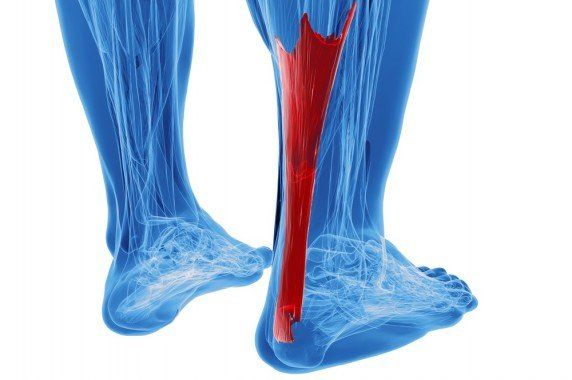

Tendinopatia ścięgna Achillesa

Tendinopatia ścięgna Achillesa